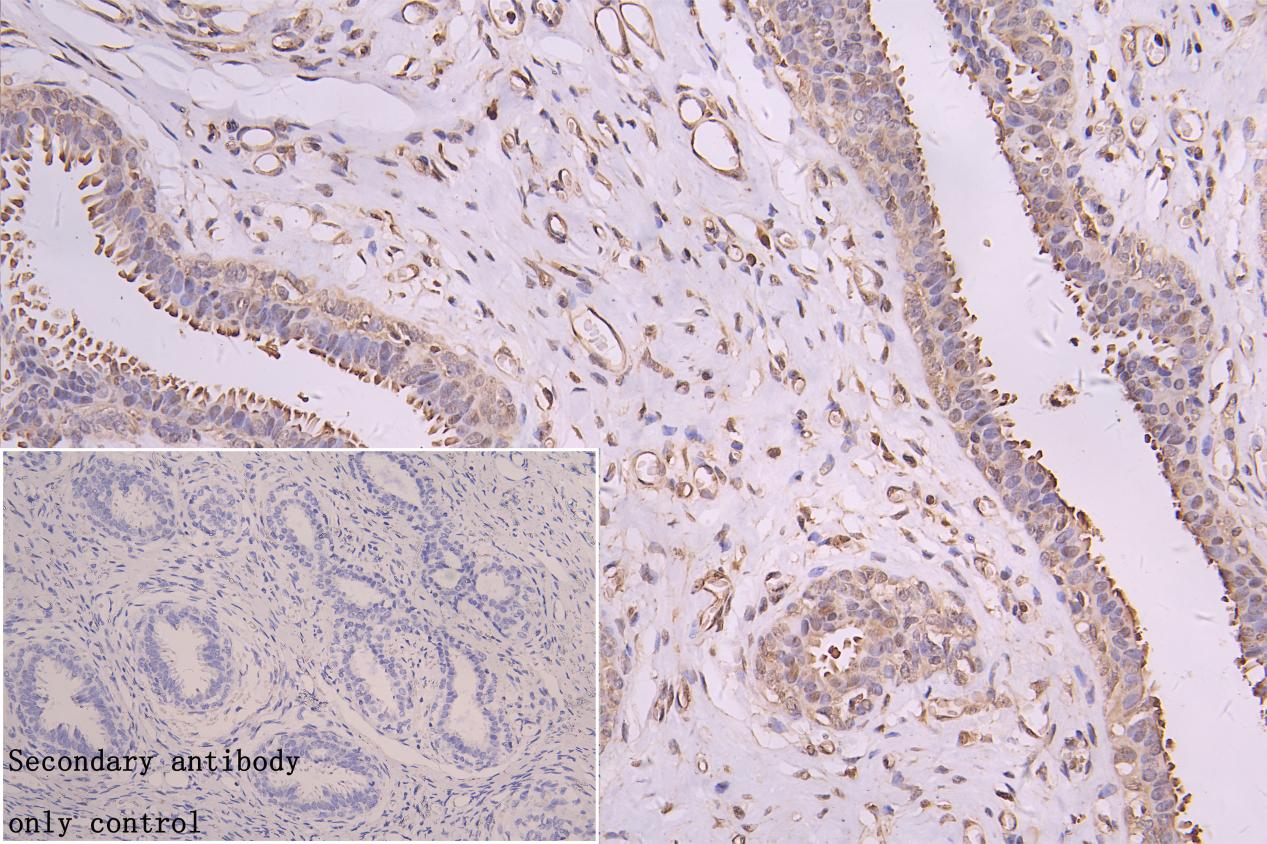

IHC image of CSB-RA616077A0HU diluted at 1:50 and staining in paraffin-embedded human breast cancer performed on a Leica BondTM system. After dewaxing and hydration, antigen retrieval was mediated by high pressure in a citrate buffer (pH 6.0). Section was blocked with 10% normal goat serum 30min at RT. Then primary antibody (1% BSA) was incubated at 4°C overnight. The primary is detected by a Goat anti-rabbit polymer IgG labeled by HRP and visualized using 0.05% DAB. Secondary antibody only control: uses 1% BSA instead of primary antibody